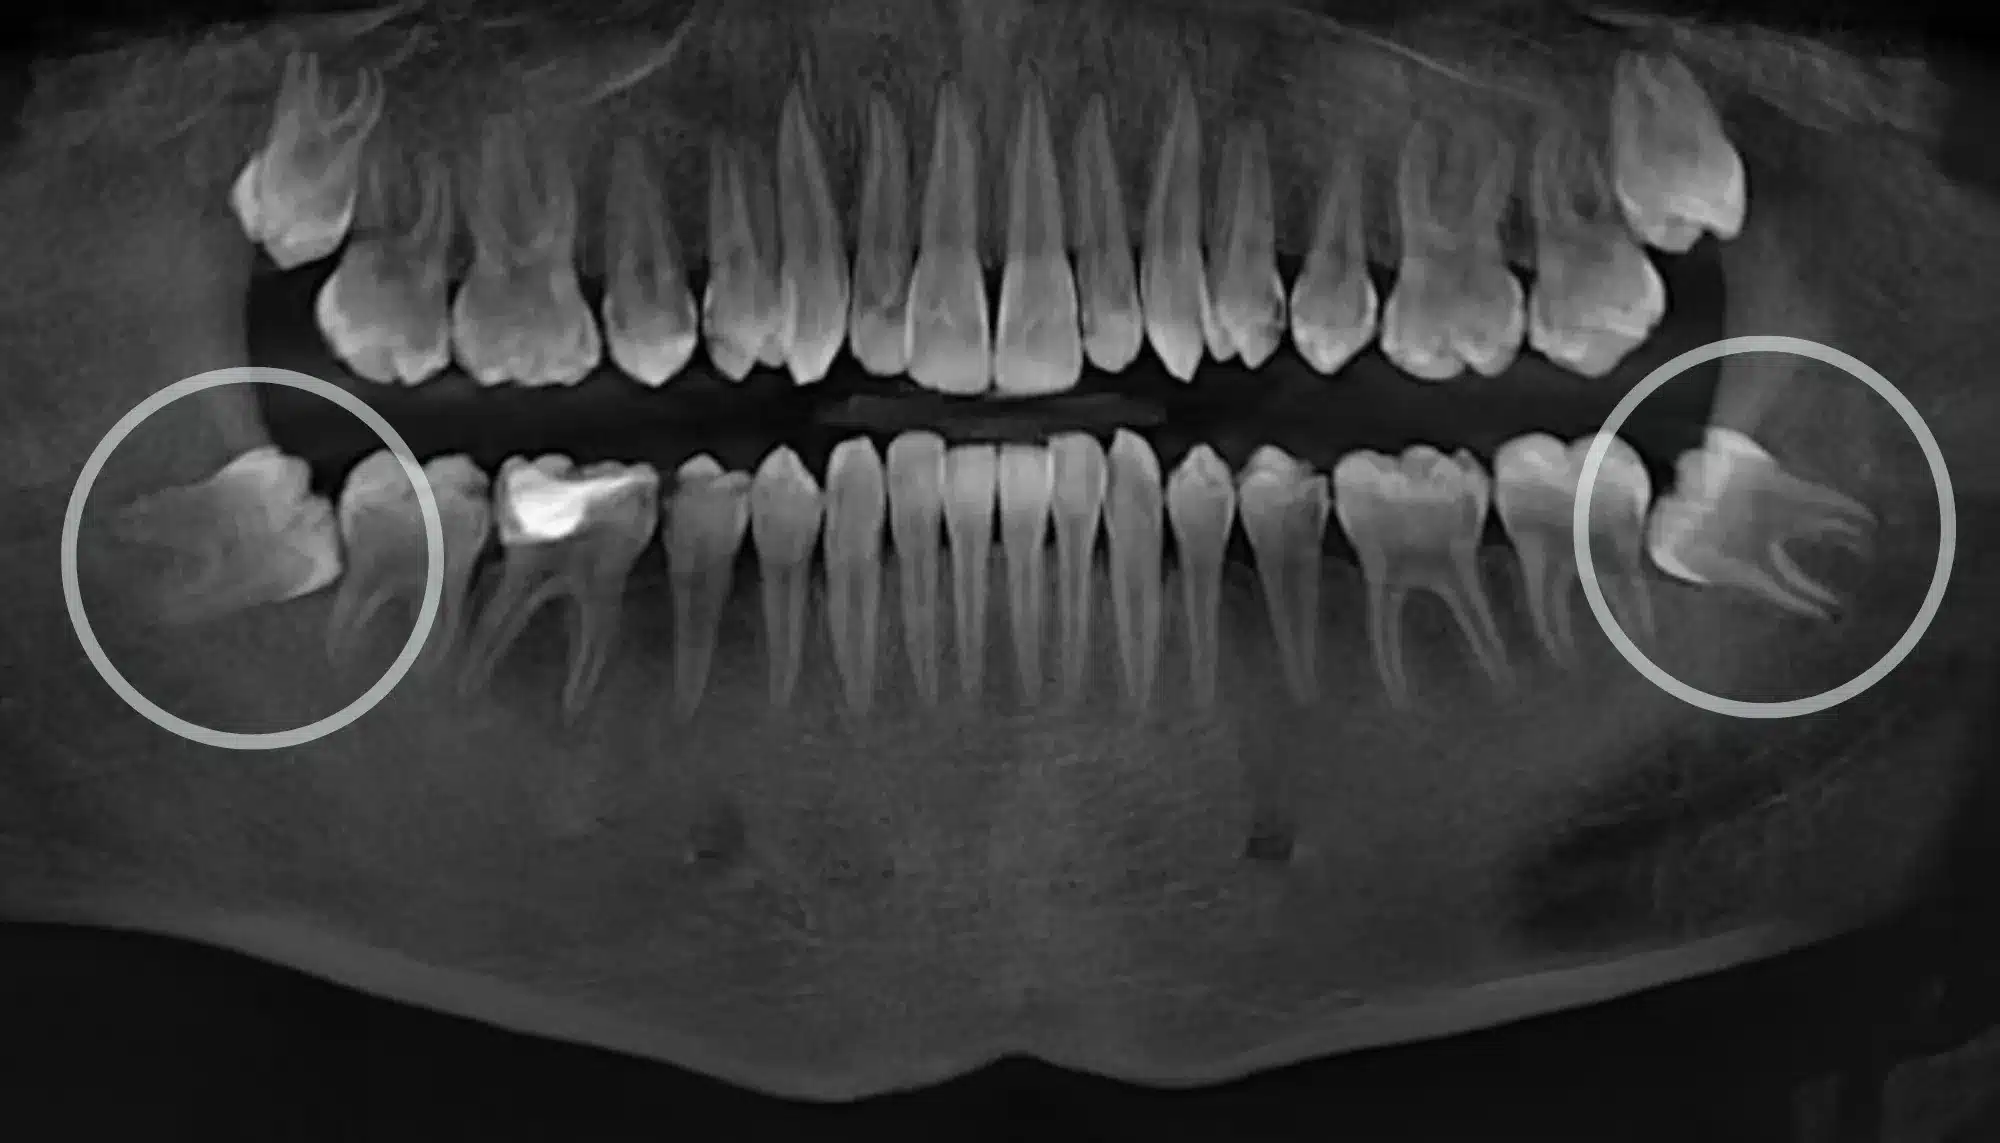

Bir 20’lik dişin çekilip çekilmeyeceğine karar verilirken, dişin çene kemiği ve diş eti içindeki pozisyonu en önemli faktördür. Dişler temel olarak üç farklı pozisyonda olabilir:

- Yarı Gömük: Dişin bir kısmının diş etini yardığı, ancak bir kısmının hala diş eti veya kemik altında kaldığı durumdur. En tehlikeli pozisyon budur çünkü diş ile diş eti arasında yiyecek artıklarının biriktiği bir “cep” oluşur. Bu cep, bakteri üremesi için ideal bir ortamdır ve sık sık ağrılı enfeksiyonlara (perikoronit) ve komşu dişin çürümesine neden olur.

- Tam Gömük: Dişin tamamen diş eti ve/veslice; veya kemik içinde kaldığı durumdur. Dışarıyla hiçbir teması yoktur. Genellikle belirti vermezler. Ancak komşu dişin köküne baskı yapıyor, kist oluşturuyor veya ortodontik bir tedaviye engel oluyorsa çekilmeleri gerekir. Aksi halde, sadece düzenli röntgen takibi yeterli olabilir.

Özellikle alt çenedeki gömük 20’lik dişlerin çekiminde, hastaların ve hekimlerin dikkate aldığı en önemli risklerden biri sinir hasarıdır. Alt 20’lik dişlerin kökleri, alt dudağa ve çene ucuna his veren “inferior alveolar” sinirine çok yakın bir konumda olabilir. Bazı durumlarda dişin kökleri bu sinir kanalının içinden bile geçebilir. Bu gibi anatomik olarak riskli vakalarda, çekim sırasında sinirde bir zedelenme, gerilme veya kopma meydana gelebilir. Bu durum, genellikle geçici, ancak nadiren kalıcı olabilen, dudakta ve çene ucunda uyuşukluk (parestezi) hissine neden olabilir. Deneyimli bir çene cerrahisi uzmanı, çekim öncesi çekilen 3 boyutlu dental tomografi (CBCT) ile dişin kökleri ve sinir arasındaki ilişkiyi detaylı bir şekilde değerlendirir. Eğer risk çok yüksekse ve diş herhangi bir soruna (ağrı, kist vb.) neden olmuyorsa, bazen dişi çekmek yerine sadece takip etme kararı alınabilir.